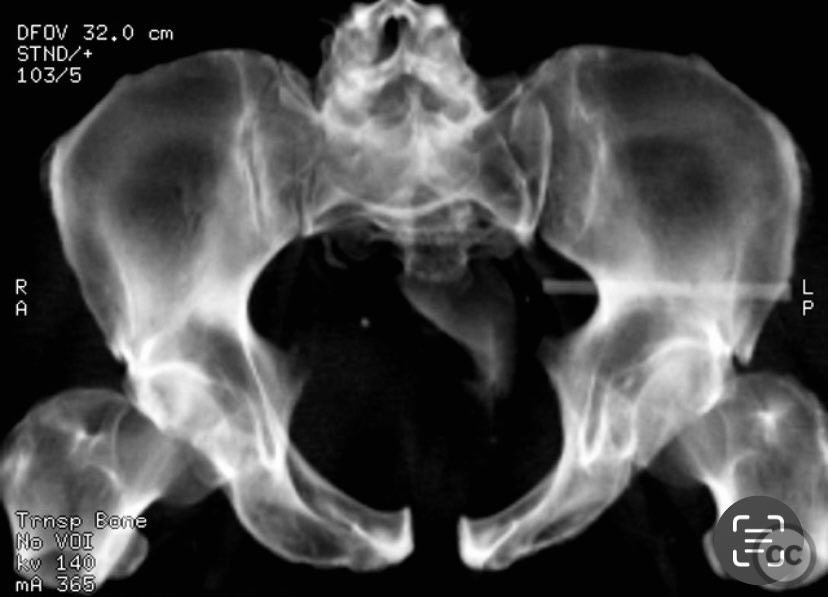

Clinical and radiological findings:  An adult patient sustained traumatic disruption of the symphysis pubis and an incomplete left sacroiliac (SI) joint injury. Initial radiographs and pelvic CT scan (performed without circumferential pelvic wrapping) demonstrated a widened symphysis pubis and an incomplete disruption of the left SI joint. The CT scan further provided information regarding bone quality, upper sacral morphology, patient body habitus, and vascular anatomy. No additional pelvic ring injuries were identified. AO/OTA classification: 61-B2.1 (lateral compression injury with incomplete posterior disruption).

Planning remarks:  The preoperative plan included open reduction and internal fixation of the symphysis pubis via an anterior approach, with provisional reduction using a pelvic reduction clamp. Indirect reduction of the SI joint was anticipated via anterior stabilization; however, preparation for percutaneous iliosacral screw fixation was considered should indirect reduction prove inadequate.